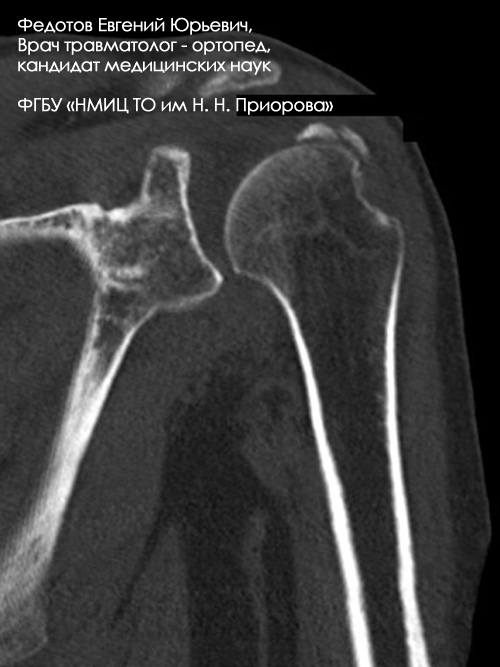

Пациентка с оскольчатым переломом верхнего отдела плечевой кости.

Рентгенограмма до операции.

Выполнена операция: металлоостеосинтез плечевой кости высокотехнологичным стержнем Targon.

Гипсовая повязка после операции не применялась, сразу после операции начата физкультура для суставов и мышц конечности.

Результат через 3 дня после операции.

Еще не сняты швы, виден отек, кровоподтеки на конечности после перелома. Пациентка уже может выполнять несложную бытовую работу, обслуживать себя без посторонней помощи.